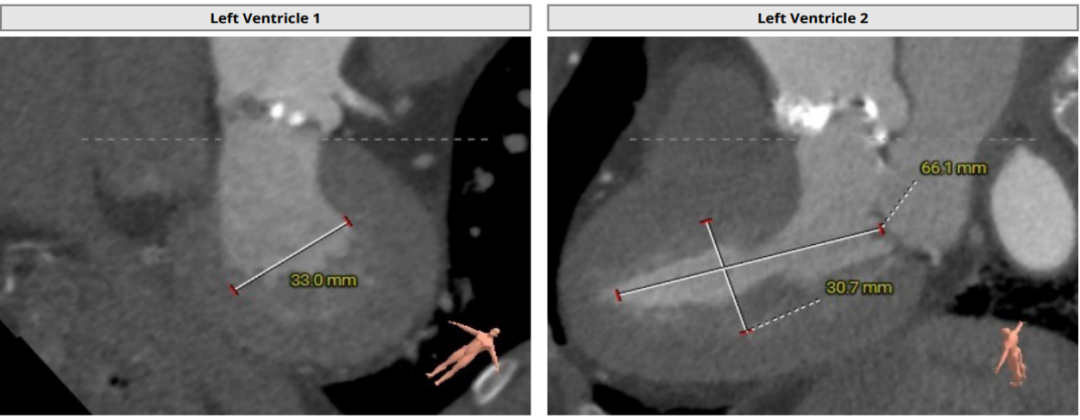

左室腔内径尚可,心室壁增厚;

冠脉阻挡风险及左室大小评估

左室腔内径尚可,心室壁增厚,射血分数67%,术中适当补液,关注血流动力学变化;